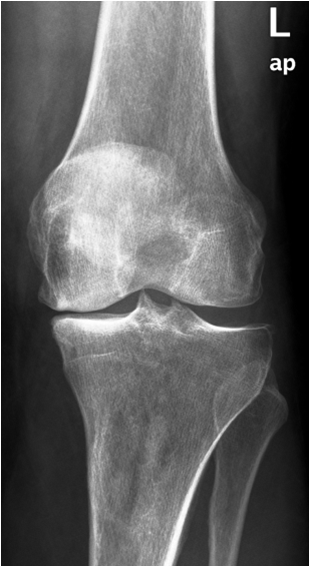

17.4. Degenerative Joint disease

Primary osteoarthritis involves weight bearing joints such as the knee, where changes are seen especially in the medial compartment and the patellofemoral compartment. In the hip changes are seen superolaterally. The tibiotalar joint is rarely significantly involved, except for changes along the anterior margin of the distal articular surface of the tibia. These are most likely posttraumatic in origin.

Fig. 13. A) Knee joint with degenerative changes. Note the sclerotic medial tibial plateau and joint space narrowing. A small osteophyte is seen on the medial femoral condyle. B.) Pelvis with marked degeneration of both hip joints. The right femoral head shows lateral osteophyte formation and is deformed. The joint space is narrow with increased subchondral sclerosis of the acetabular roof. The left hip has a marked joint space narrowing and lateral osteophyte formation. The femoral head shows increased density due to sclerotic areas and irregularity.